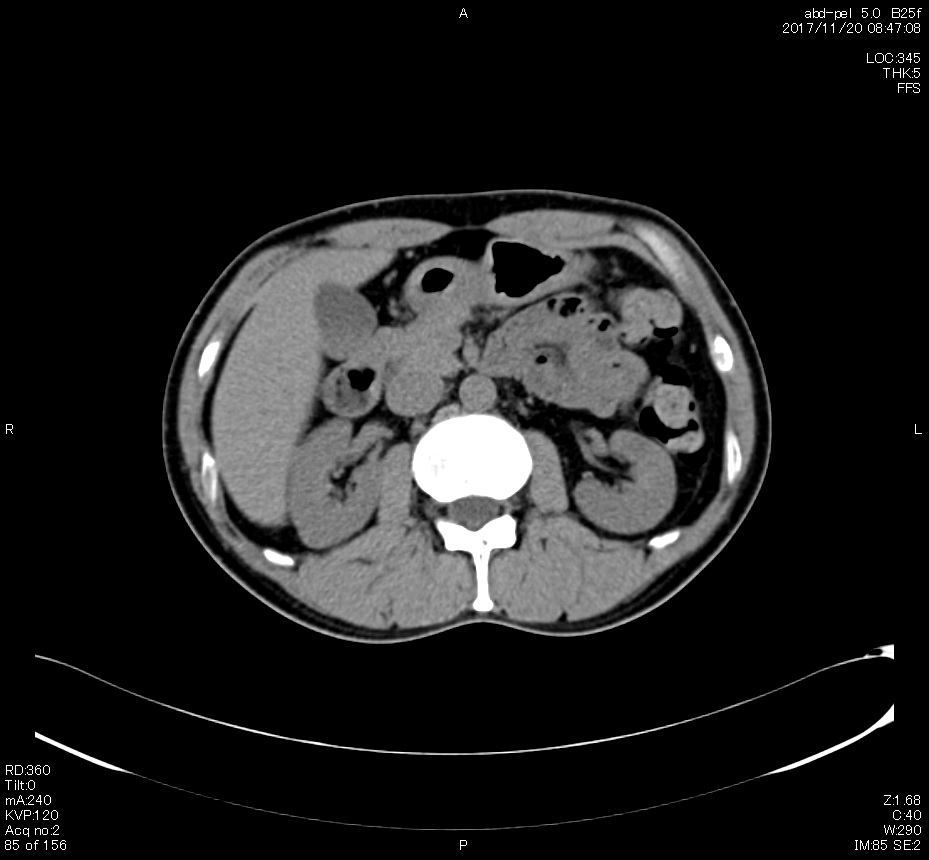

とうとうやってきた、この日が。

2006年入院治療の退院日から10年。 かなり大きな節目なんだが、なんだろうこの軽い感じは(笑)。 「10年生きたんだぁ」くらい。 変わったような変わっていないような。 当時は10年後なんて全く考えていなかった。 今も10年後は考えていないが・・・。 退院前日の2006/10/31は46.6kgだった。 今日計ったら54.8kg。体脂肪は16.6%。 とても健康にストレスなく生活できていることに、治療当時から現在に至るまで、関わった人全員に感謝の気持ちです。 マーカー、CT画像、問題なし!! 血液検査結果もほとんど文句なしの正常値。 そうだなぁ、数値に出ない異変としては、肩凝りかなぁ。 一旦夏になくなったと思ったが、初秋から再発。 マウスを左手にしたり、シップ貼ったり、最近はホッカイロ貼ったり。 で、一向に良くなる気配がない。 やはり四十肩なのか。 でも肩の可動域は問題ない。動かせないような痛みも無い。 結局色々考えてたどり着いたのは「変形性頚椎症」ではないかと。 肩凝りや頭痛がダラダラと続くようになるという症状がピッタリ当てはまる。 さて、改善策がなかなか難しい。 整形外科行ってもレントゲン撮って湿布をくれるだけだろう。 そんなことに大金を出すならまずは300円/回のプールで泳ごうと思う。 重力から開放して全身運動をするのが一番良いらしい。 2015年の目標は少しでも良いから水泳を再開する、だな。 マーカー、CT画像、問題なし!! 通常の血液検査結果も文句なしの正常値がズラ~っと並んだ!! 間違いなくヨメの食事のおかげである。ほんとうに感謝である!! ちなみに最近少々腰周りの肉付きが気になっていたのだが・・・。 左から2013年12月、2013年06月、2012年12月と背骨の位置は合わせて並べてみた。 6月まではあまり変化がなかったが、この半年で明らかに違う。 背中側の脂肪がやや増えてはいる。 でも最も大きな違いは、腸なのか、やたらと内臓が膨れている・・・。 一言で言うと食べすぎ?!?! 食事は野菜中心ではあるが、確かによく食べているw。 せっかくスーツのウエストを詰めたんだからこれ以上にならないようにしたい。 「腹八分目を心がける」かな。